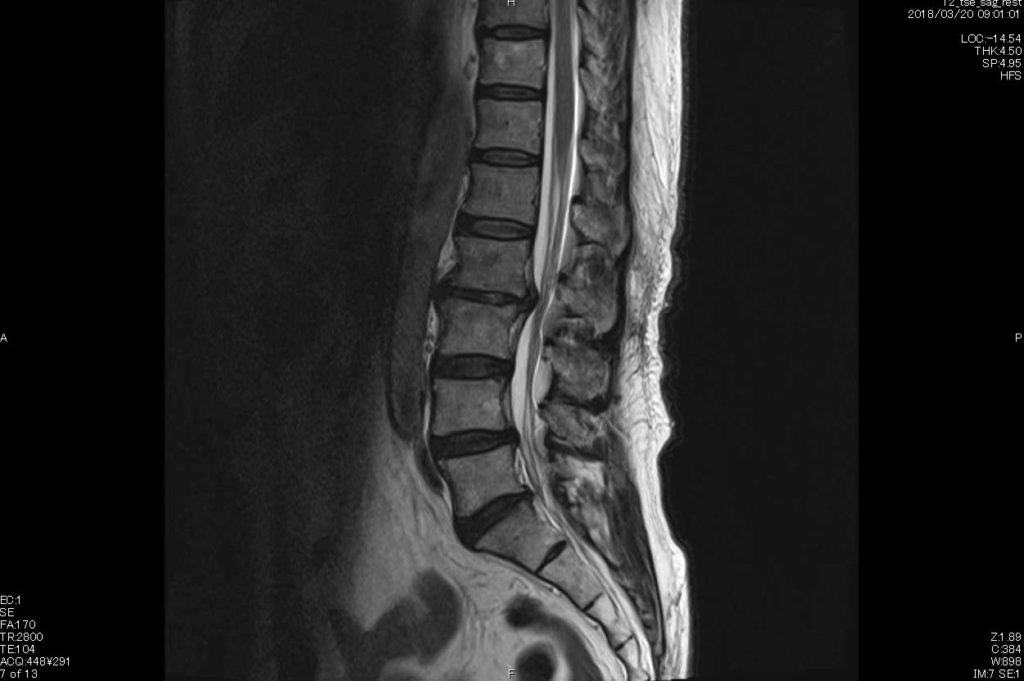

レントゲンでは腰椎4番のすべり症が確認されるものの、MRI画像ではすべりの補正作用が強く、またゴルフを好んでされていたため、腰椎の2番が椎間板で神経を圧迫していました。

2015年撮影MRI 椎間板の突出が鋭角に飛び出しているのがわかる。

2018年撮影MRI 突出が丸みを帯び減少がみられる。この頃には症状の7〜8割が消失。

初めの2週間は4番のすべりがあるので、5番の矯正を行いすべりの安定化を促しました。この時点では症状の改善は見られません。2週間を経過した頃から腰椎2番の矯正を行いました。また、患者様には半年はゴルフは控えるようにお願いしました。施術開始から約1か月経過したあたりから、症状が半減しました。最初はカイロプラクティックの施術に懐疑的であった患者さまも、このあたりから完全に信用してくださるようになりました。そして半年後には、症状の70%が消失し、本当に喜んでいただきました。施術と同時に体感トレーニングも指導させていただき、6年経過した現在は、ゴルフもコンペでご一緒させていただくほど回復されました。